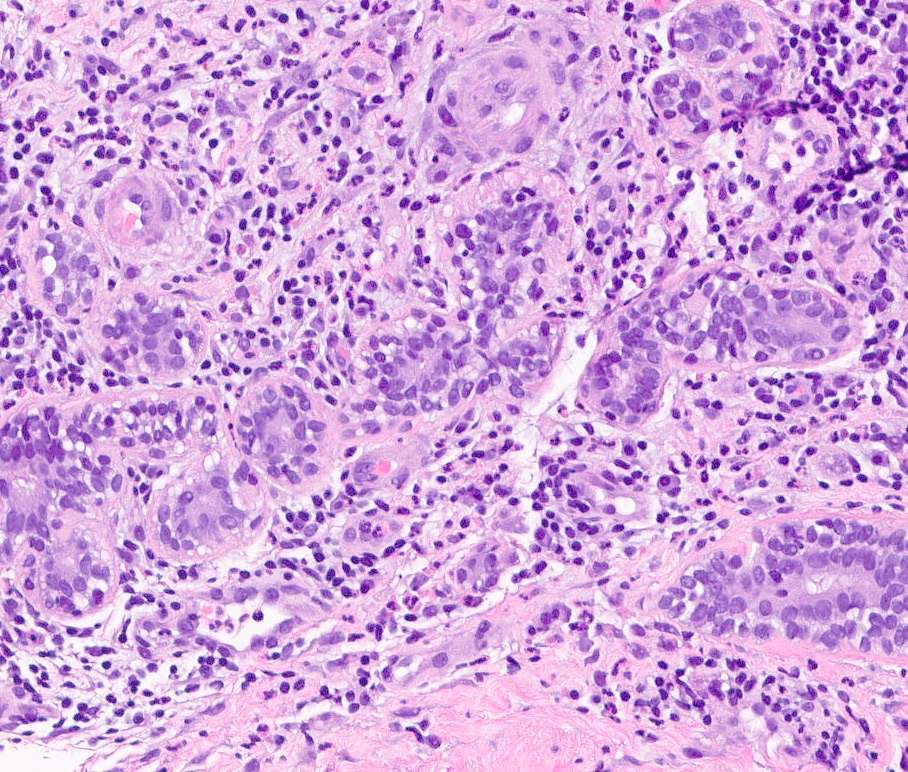

Microscopic (histologic) description

- Mixed dense inflammatory infiltrate, predominantly neutrophils, in breast tissue

- May obscure underlying normal breast tissue

- Tissue necrosis may be present

- Gram stain for microorganisms may reveal bacterial forms (gram positive cocci) associated with neutrophilic infiltrate

- Granulation tissue and chronic inflammation with resolution

- Lymphocytes, giant cells and granulomas are not typical (J Pathol Transl Med 2015;49:279)

Microscopic (histologic) images

Contributed by Kristen E. Muller, D.O.

Contributed by Ayesha Farooq, M.B.B.S. and Julie Jorns, M.D. (Case #515)